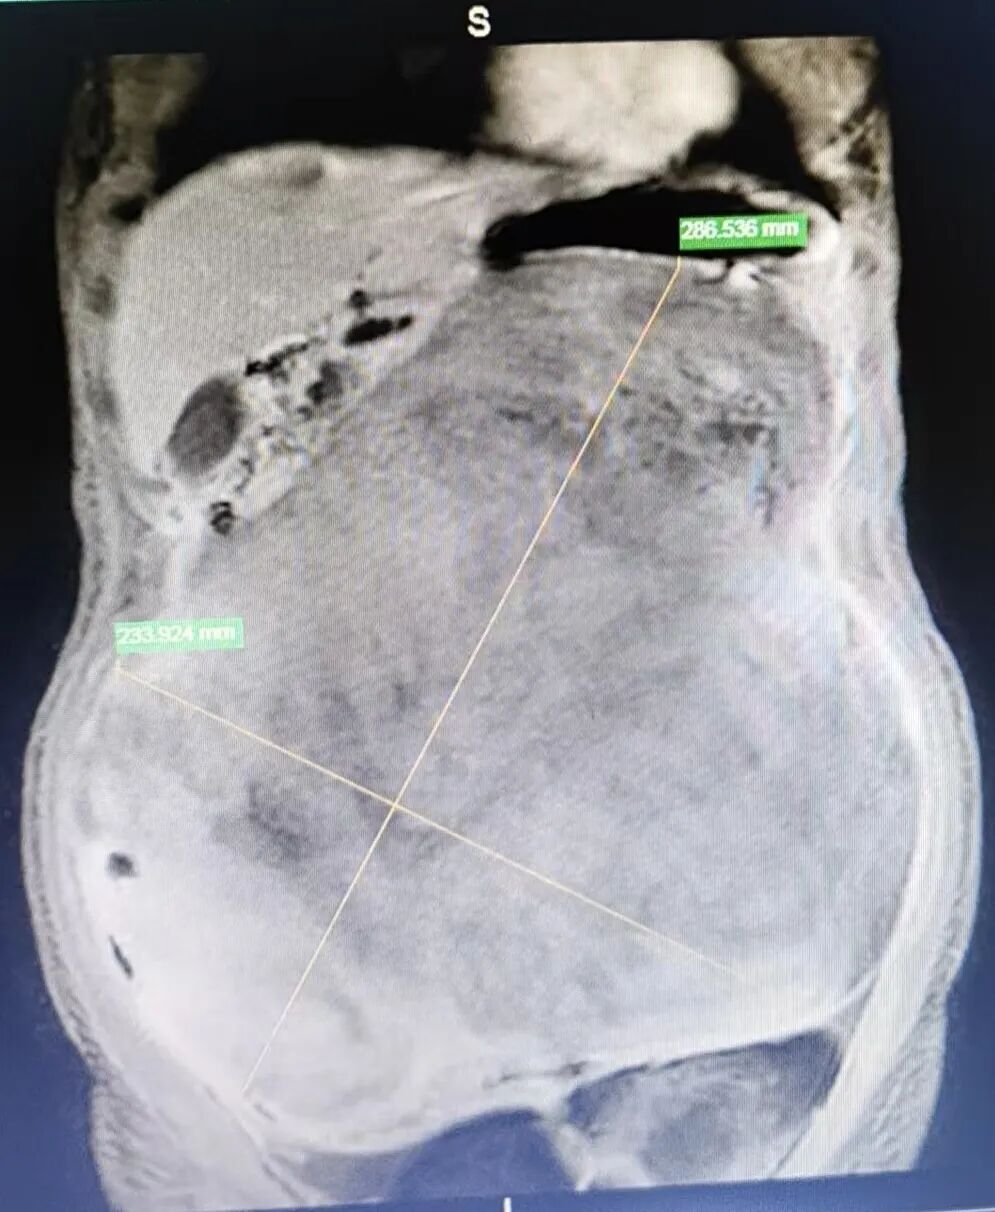

患者为34岁女性,因腹胀2月余来粤东医院就诊,经检查发现腹腔内巨大肿瘤,肿瘤体积巨大,几乎占据整个腹腔局盆腔空间,且与腹腔内脏器形成多处致密粘连,瘤体被小肠肠管紧密缠绕,底部更是直接压迫腹主动脉、下腔静脉及肠系膜血管等重要血管。这一病情不仅极大增加了手术操作难度,更暗藏血管损伤、大出血等极高风险,对手术团队的技术水平与协作能力提出了严峻挑战

术前影像学检查提示腹腔巨大肿瘤